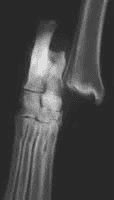

X-rays are recommended to rule out fractures and evaluate surrounding structures, although the diagnosis is often made based on examination findings alone.

X-ray changes with Partial and Complete Ruptures